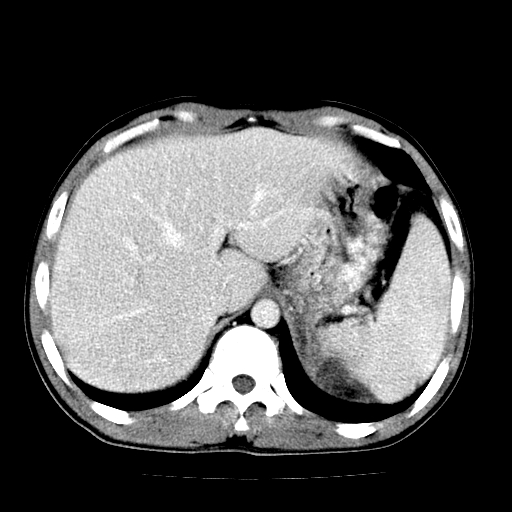

以下是引用天南地北在2007-4-30 13:36:00的发言:[br]支持慢性胰腺炎伴有假性囊肿

以下是引用andymaomao在2007-4-30 14:28:00的发言:[br]支持:1.慢性胰腺炎并假性囊肿形成可能;[br] 2.左肾形态稍增大,旋转不良。